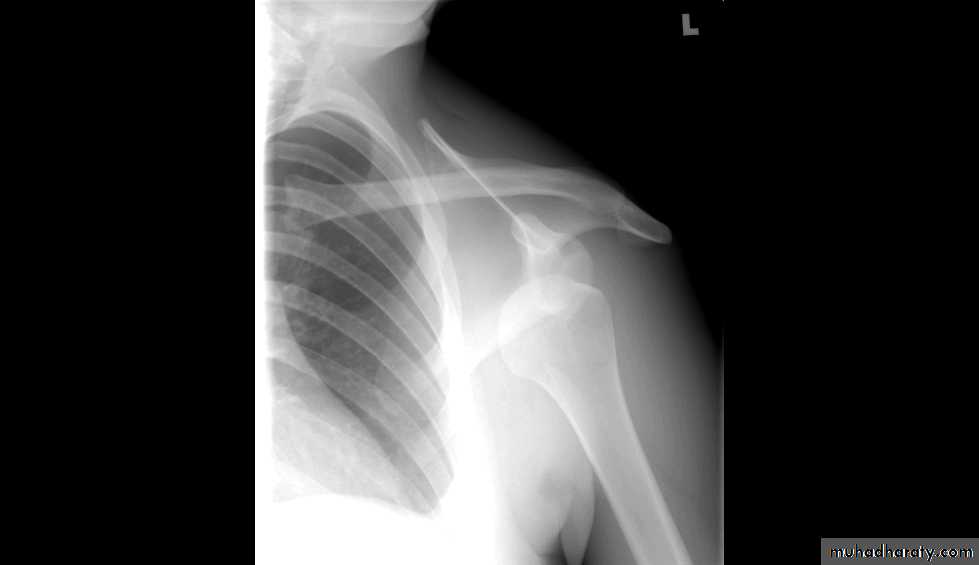

X RAYS

Practical sessions

DIAGNOSIS???

Shoulder Dislocation/Anterior Instability

Humeral head dislocates from glenoid fossa

Almost always anterior (95%)

Usually traumatic with injury to capsule-labrum complex